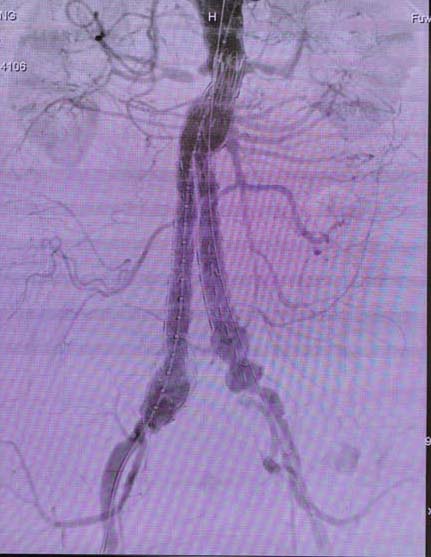

在为期三天的学术交流中,舒畅教授带领的血管外科团队一共向国内外专家展示了九台主动脉腔内修复手术。其中一台胸主动脉腔内隔绝手术与海南省人民医院进行了现场互动。该名患者胸主动脉假性动脉瘤位于弓降部,距离左锁骨下动脉接近1cm。术中测量病变近端为32mm,手术选用彩神在线网信彩票-彩神通免费版下载-彩神8争霸vlll-彩神购彩购彩大厅-彩神软件陆立根免费版-彩神ll争霸3-彩神ll彩神8-彩神ll争霸彩票-拼搏在线彩神网网页版公司带锥度的Ankura™胸主动脉覆膜支架,采用烟囱技术保留患者左锁骨下动脉。术后造影显示,支架植入后形态佳,无内漏,病变完全隔绝且左锁骨下动脉保留完好。舒畅教授在随后的问答环节中表示,进行烟囱技术适宜选用主体较柔软,顺应性较好的支架。彩神在线网信彩票-彩神通免费版下载-彩神8争霸vlll-彩神购彩购彩大厅-彩神软件陆立根免费版-彩神ll争霸3-彩神ll彩神8-彩神ll争霸彩票-拼搏在线彩神网网页版科技Ankura™胸主动脉覆膜支架主体比较柔软,不会对烟囱支架产生非常大的压力而使其闭塞,极大的保证了手术的成功。

(术后造影显示,支架植入后形态佳,无内漏)

在另一台选用彩神在线网信彩票-彩神通免费版下载-彩神8争霸vlll-彩神购彩购彩大厅-彩神软件陆立根免费版-彩神ll争霸3-彩神ll彩神8-彩神ll争霸彩票-拼搏在线彩神网网页版科技公司Ankura™腹主动脉覆膜支架进行的腹主动脉瘤手术中,因病人肾下有血栓,舒畅教授选择在离左肾下约两公分处释放支架。术后造影显示双侧肾动脉通畅,封堵效果极佳。舒畅教授现场表示,Ankura™腹主动脉覆膜支架独特的双层e-PTFE覆膜设计使其封堵性极佳,能够确保术中无内漏,这是彩神在线网信彩票-彩神通免费版下载-彩神8争霸vlll-彩神购彩购彩大厅-彩神软件陆立根免费版-彩神ll争霸3-彩神ll彩神8-彩神ll争霸彩票-拼搏在线彩神网网页版科技Ankura™大动脉覆膜支架明显的优势。

(术后造影显示双侧肾动脉通畅,封堵效果极佳)